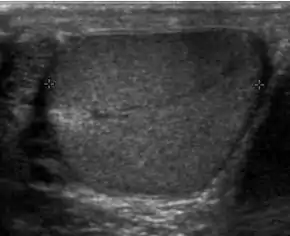

Doppler ultrasound of epididymitis, seen as a substantial increase in blood flow in the left epididymis (top image), while it is normal in the right (bottom image). The thickness of the epididymis (between yellow crosses) is only slightly increased (7 mm).

Doppler ultrasound of the scrotum of the same case, in the axial plane, showing orchitis (as part of epididymo-orchitis) as hypoechogenic and slightly heterogenic left testicular tissue (right in image), with an increased blood flow. There is also swelling of peritesticular tissue.